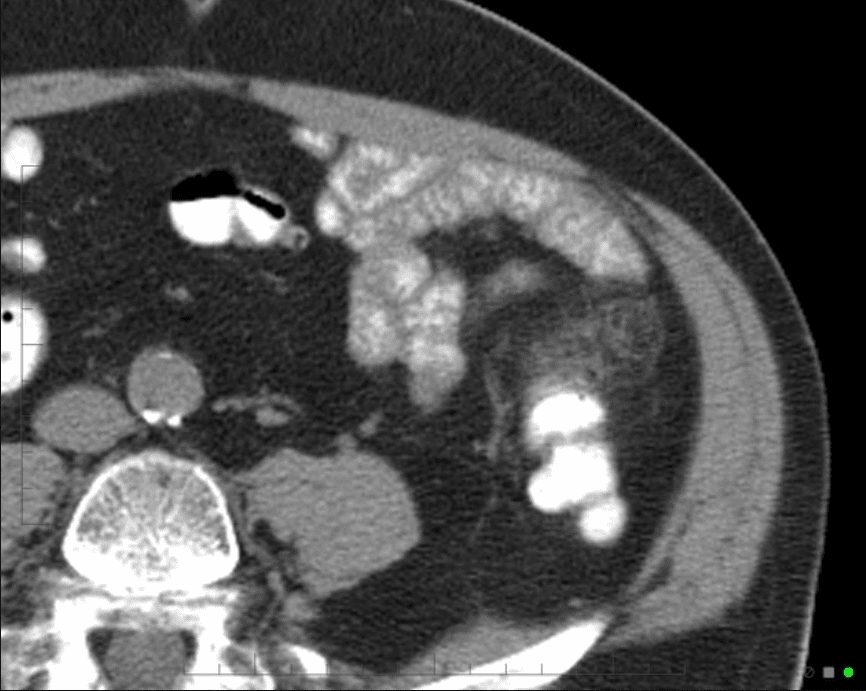

Viêm túi thừa

Viêm túi thừa - Ảnh 4

» Thông tin: Nam giới – 25 tuổi.

» Lâm sàng: Đau hố chậu trái.